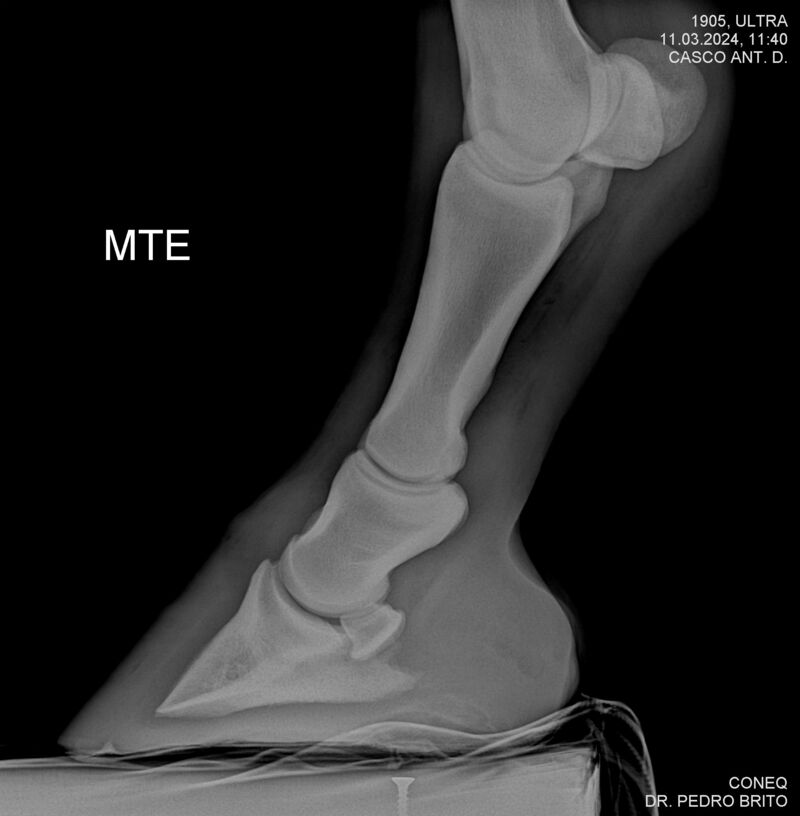

ULTRA DO CACH

Raça: BRASILEIRO DE HIPISMO

Sexo: CASTRADO - CASTRADO

Nascimento: 22/11/2020

Altura Aproximada: 1,67

Pel.: CASTANHO

Registro: 25966-BH

Vend.: HARAS CACHOEIRINHA

Local : PIRASSUNUNGA/SP